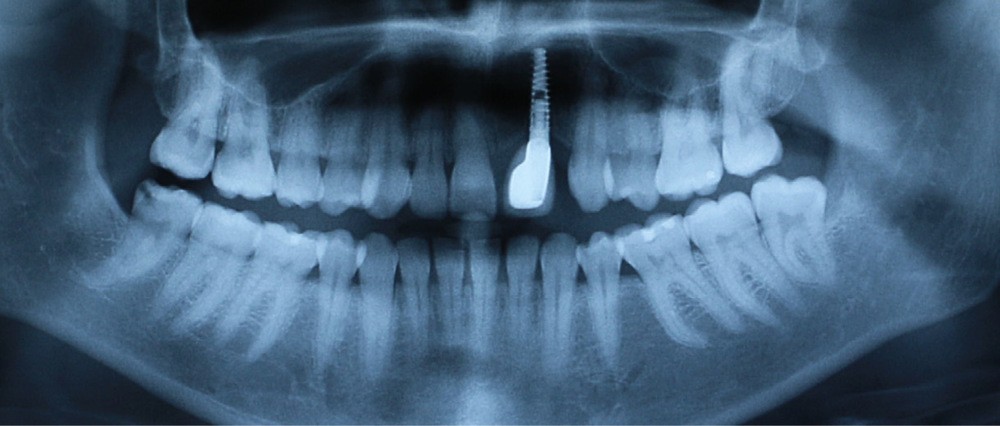

À la suite d’un accident de la voie publique il y a plusieurs années, le secteur antérieur maxillaire a été traumatisé, 21 et 22 ont été expulsées, et 11 et 12 présentent d’importantes résorptions radiculaires externes inflammatoires visibles à la radiographie panoramique (fig. 1).

- au niveau dentaire : une arcade maxillaire asymétrique avec déviation du milieu maxillaire à gauche. On note l’absence de 21, 22, 25, 35 et 45, une classe II droite et gauche avec infraclusion antérieure et la présence d’un implant en place de 21 avec un diastème de 3 mm entre 21 et 23 (fig. 3) ;